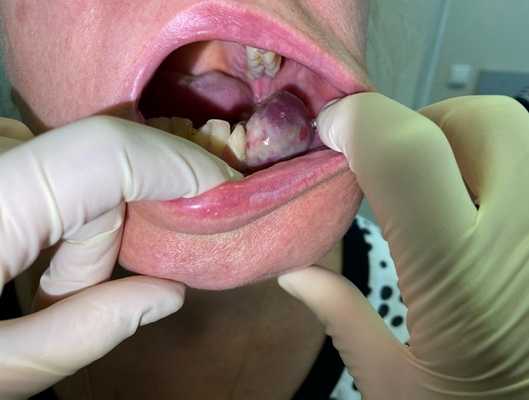

Примеры сарком мягких тканей головы и шеи

Остеогенная саркома альвеолярного отростка верхней челюсти

Остеогенная саркома нижней челюсти

Плеоморфная саркома мягких тканей шеи справа